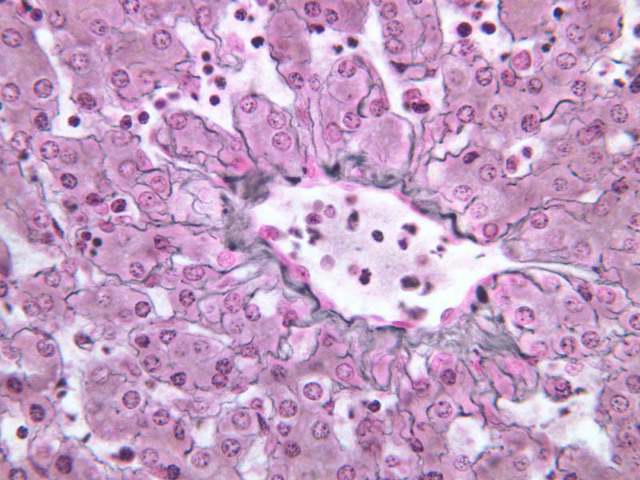

Although H & E staining permits ready identification of the islets of Langerhans, it does not permit differentiation of the various cell types that comprise the islets (B-36, H&E [10x, 20x, 40x-labeled]). There are no slides in the class collection that permit identification of all of the cell types of the endocrine pancreas. However, the sections on slides B-37 and B-40 permit specific identification of two cell types. Slide B-37 has been stained by the aldehyde fuchsin technique, which lends a magenta coloration to the granules of the insulin-producing B-cells. All other cells in the islets stain a dirty orange color (B-37 [10x, 20x, 40x] [10x, 20x, 40x]). Most of these orange-colored cells are the glucagon-secreting A-cells; however, you should bear in mind that somatostatin-secreting D-cells, as well as APUD cells that secrete pancreatic polypeptide are also scattered about the islet. The section on slide B-40 has been prepared by a silver impregnation method that renders some of the APUD cells in the islets (which appear as “clear cells” in ordinary preparations) dark brown or black (B-40 [10x, 20x, 40x]).

9 Islet of Langerhans IL, (circled area) H&E, Ink/H&E b36 interlobular duct pancreas 10x labeled.jpgB36, Pancreas, 10x; b36 islets of langerhans pancreas 40x labeled.jpgB36, Pancreas, 40x; b39 capillary beds pancreas 20x ink he labeled.jpgB39, Pancreas, 20x

10 A Cells A H&E b36 islets of langerhans pancreas 40x labeled.jpgB36, Pancreas, 40x